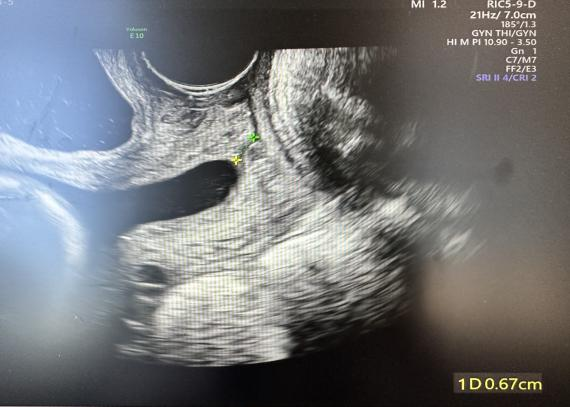

术前宫颈中上段呈U形,下段有效宫颈管长约0.67cm

为什么要扩张宫颈孕妈不能承受之重:宫颈机能不全怎么办?_https://www.jmylbn.com_新闻资讯_第5张